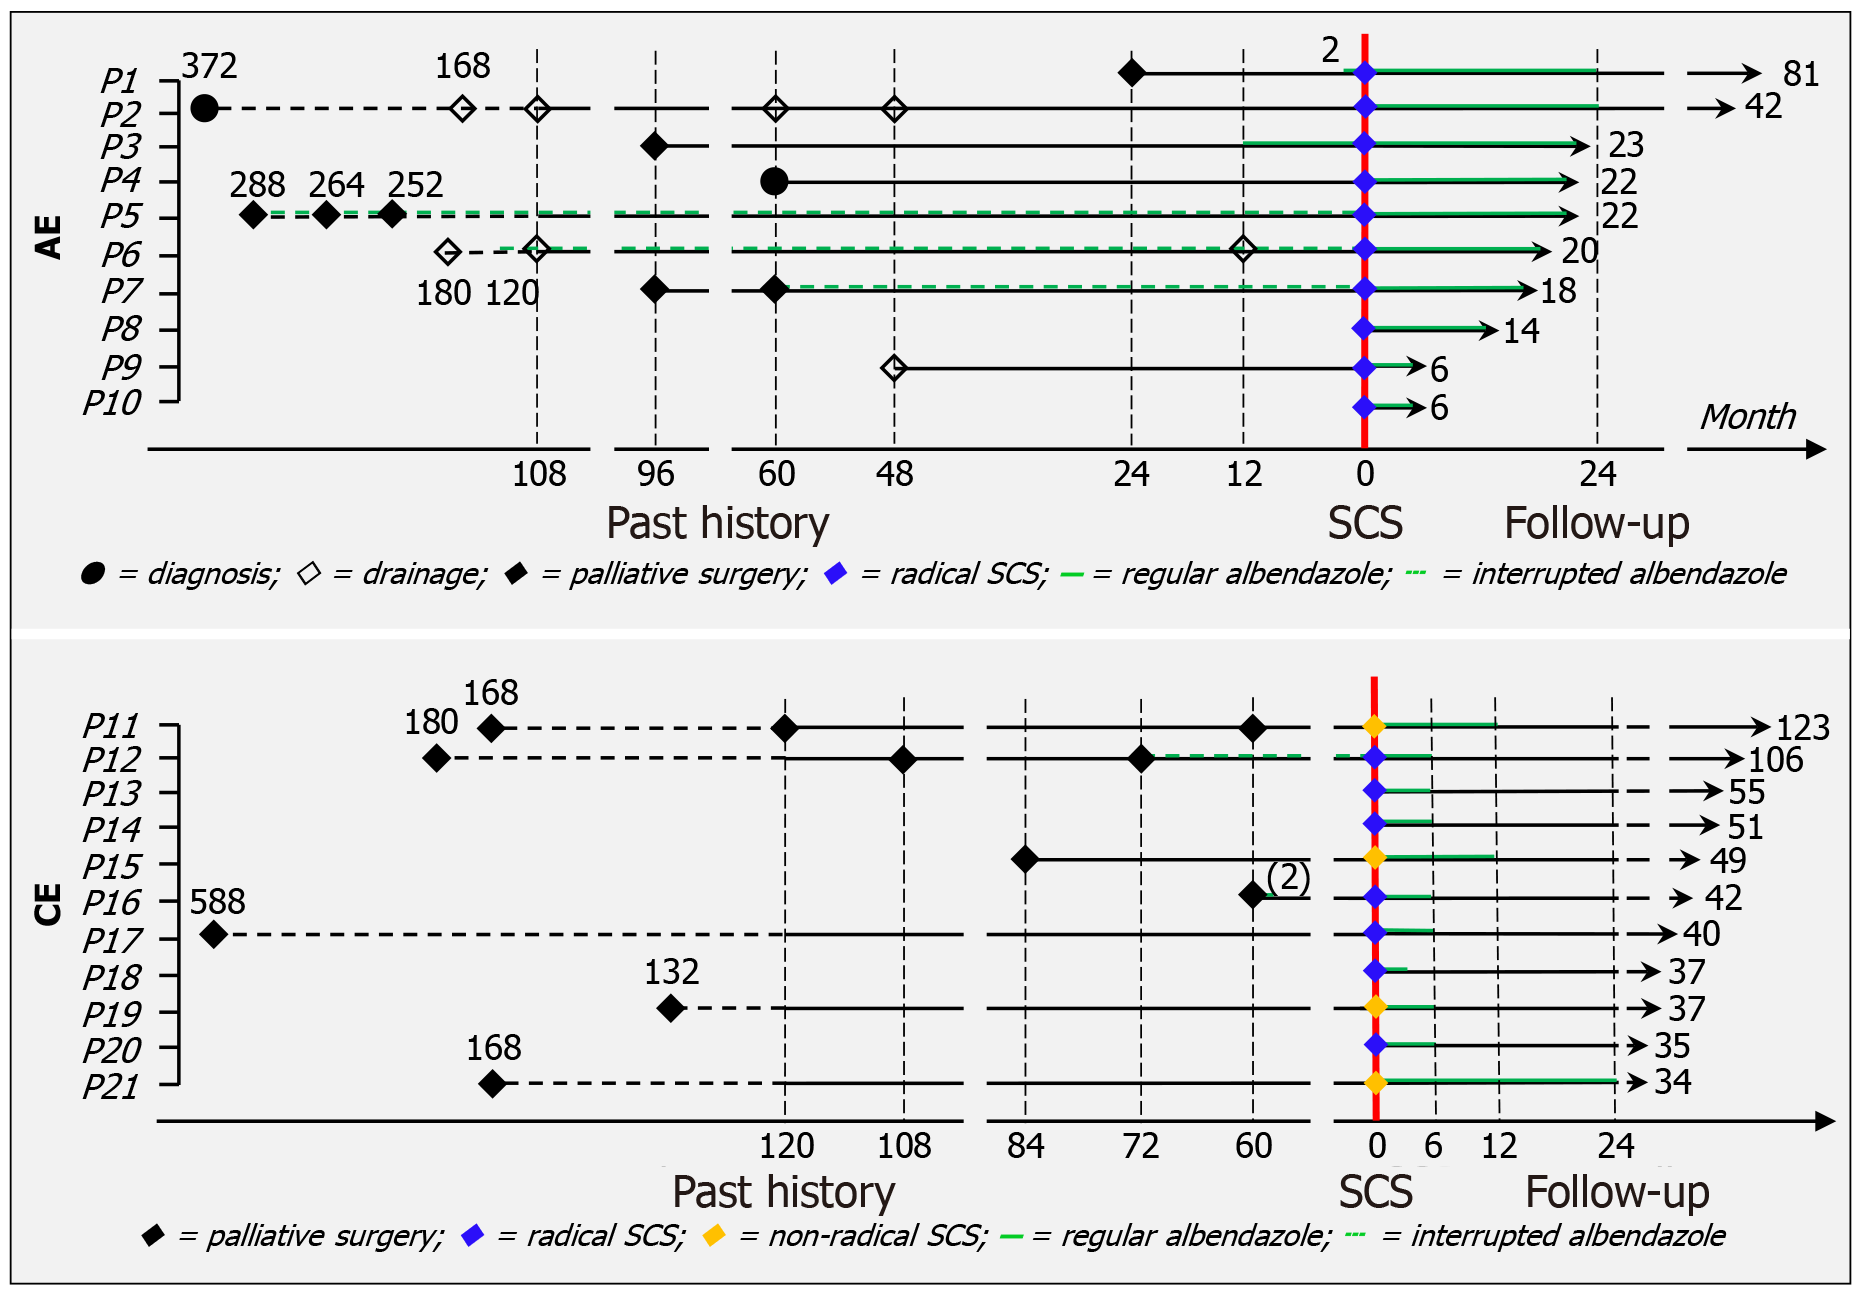

Figure 1 Treatment timelines.

The majority of patients with alveolar echinococcosis (AE) underwent multiple palliative interventions prior to presentation. All AE patients were deemed suitable for radical simultaneous combined surgery (SCS). Postoperatively, all AE cases adhered to expert consensus guidelines and achieved cure. Conversely, two patients with cystic echinococcosis (CE) received repetitive palliative surgeries, and five others experienced recurrence following a single surgical procedure. Radical SCS was feasible in only seven CE patients. Nonetheless, all CE patients achieved clinical cure. AE: Alveolar echinococcosis; CE: Cystic echinococcosis; SCS: Simultaneous combined surgery.